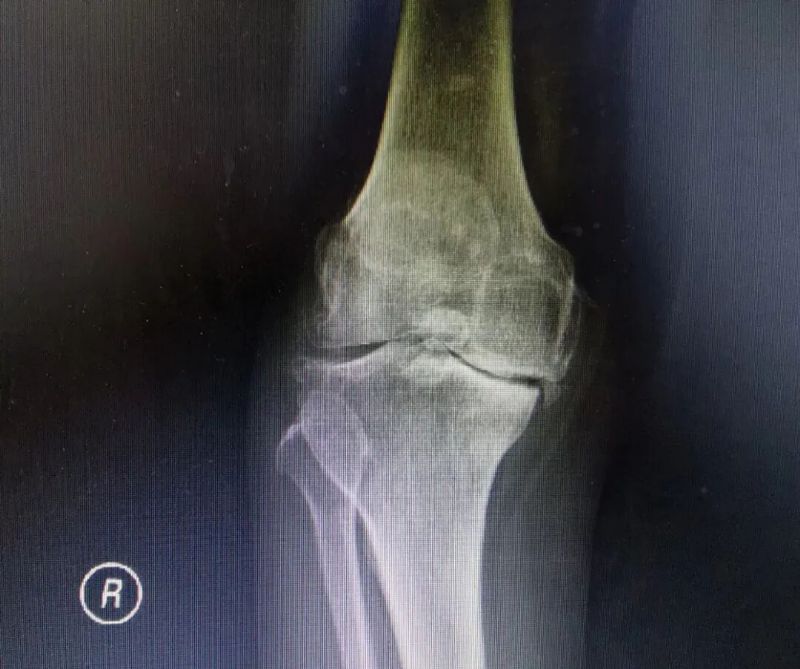

影像學(xué)檢查是診斷的重要手段。X線檢查就像給關(guān)節(jié)拍了一張“照片”,能夠清晰地顯示關(guān)節(jié)間隙變窄、骨質(zhì)增生、軟骨下骨硬化等典型表現(xiàn)。而MRI檢查則更像是一部“高清攝像機(jī)”,能更清晰地觀察關(guān)節(jié)軟骨、半月板、滑膜等軟組織的病變情況,為醫(yī)生提供更準(zhǔn)確的診斷依據(jù)。